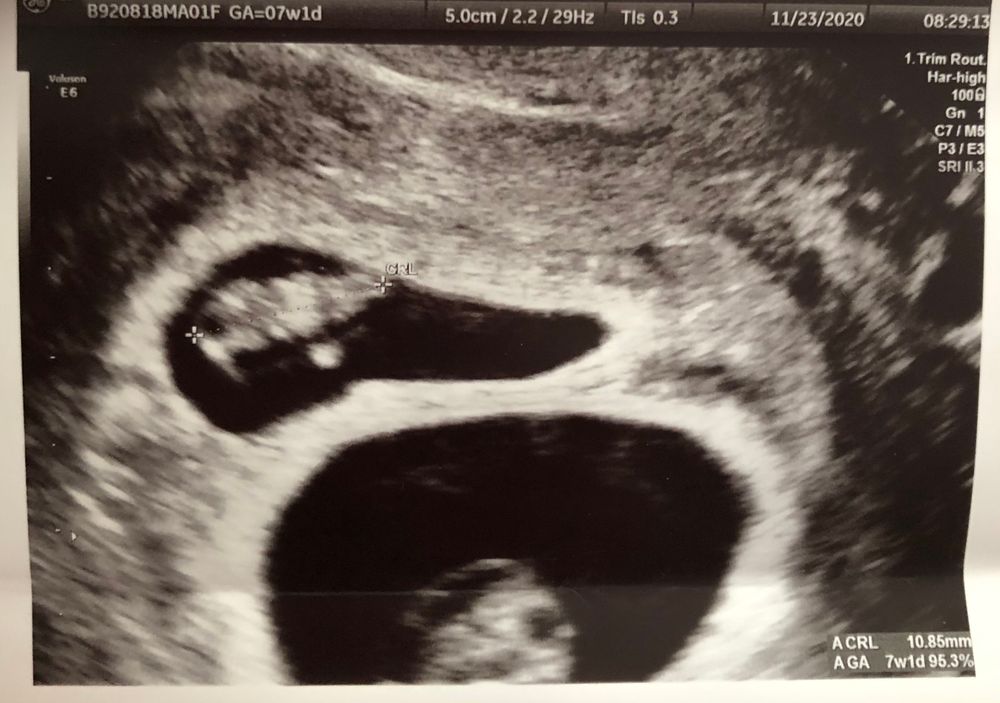

32 ДПП - на узи показалась двойня 🤪

Ну, такая гематома рассосётся только через 9 месяцев 🤣 Поздравляю 🎉

Женечка, спасибо! 🌹 гематома есть и настоящая тоже 😐 но вторая приятно удивила 🤣🤣